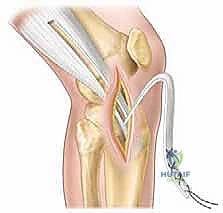

شكل 3: تجهيز الطعم الوتري (Graft Preparation) بعناية فائقة. يتم اختيار الطعم المناسب وتجهيزه ليكون بالقوة والسمك المناسبين لركبة الطفل.

شكل 4: تحديد مسار النفق العظمي بدقة متناهية تحت توجيه الأشعة لضمان بقائه بعيداً عن صفيحة النمو الحساسة.